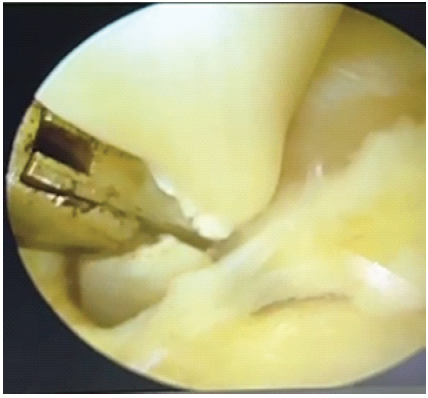

A 4.0-mm 30° arthroscope was introduced through the posterolateral portal. The FHL tendon was visualized at the level of the posterior ankle, just posterior to the talus. Dynamic testing by flexion of the great toe was performed to confirm the tightness and tethering of the FHL tendon during passive dorsiflexion of the ankle (Figs. 4 and 5).

Figure 4: Identification of the flexor hallucis longus tendon.

Figure 5: endoscopic tenotomy of the flexor hallucis longus tendon.

The FHL tendon sheath was carefully released using a shaver and radiofrequency device. A partial tenotomy of the FHL tendon was performed at the zone of entrapment. Intraoperatively, correction of the deformity was confirmed by passive ankle movement. The portals were closed with nylon sutures.